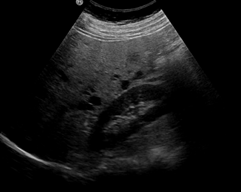

1) 초음파

가장 흔하게 사용되는 검사는 초음파로 간낭종 내부의 상태와 크기를 쉽게 확인할 수 있습니다. 검사 중에 방사선 노출의 위험이 없고, 쉽게 휴대할 수 있어 검진에 많이 사용되고 있습니다.